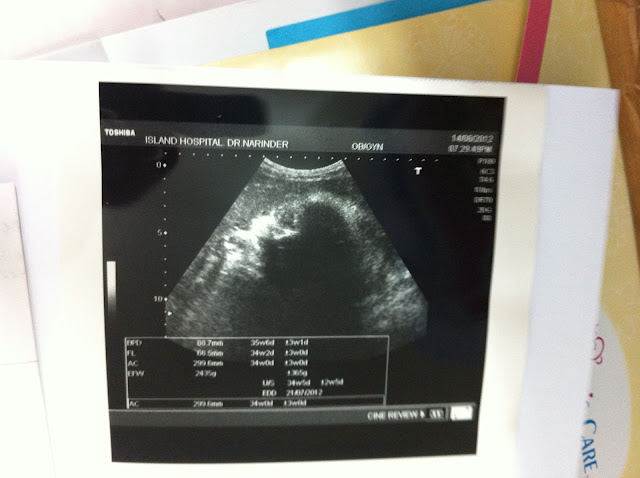

今天去产检回来

医生说宝宝3.4 or 3.5kg

头蛮大,也是鼓励我开刀

已经定了这个拜五早上九点剖腹生产

七点半报道,大概九点十五分宝宝会出来

我现在也是37w4d 头多大我不懂

但,3.4或3.5kg还真的蛮肥的。。haha